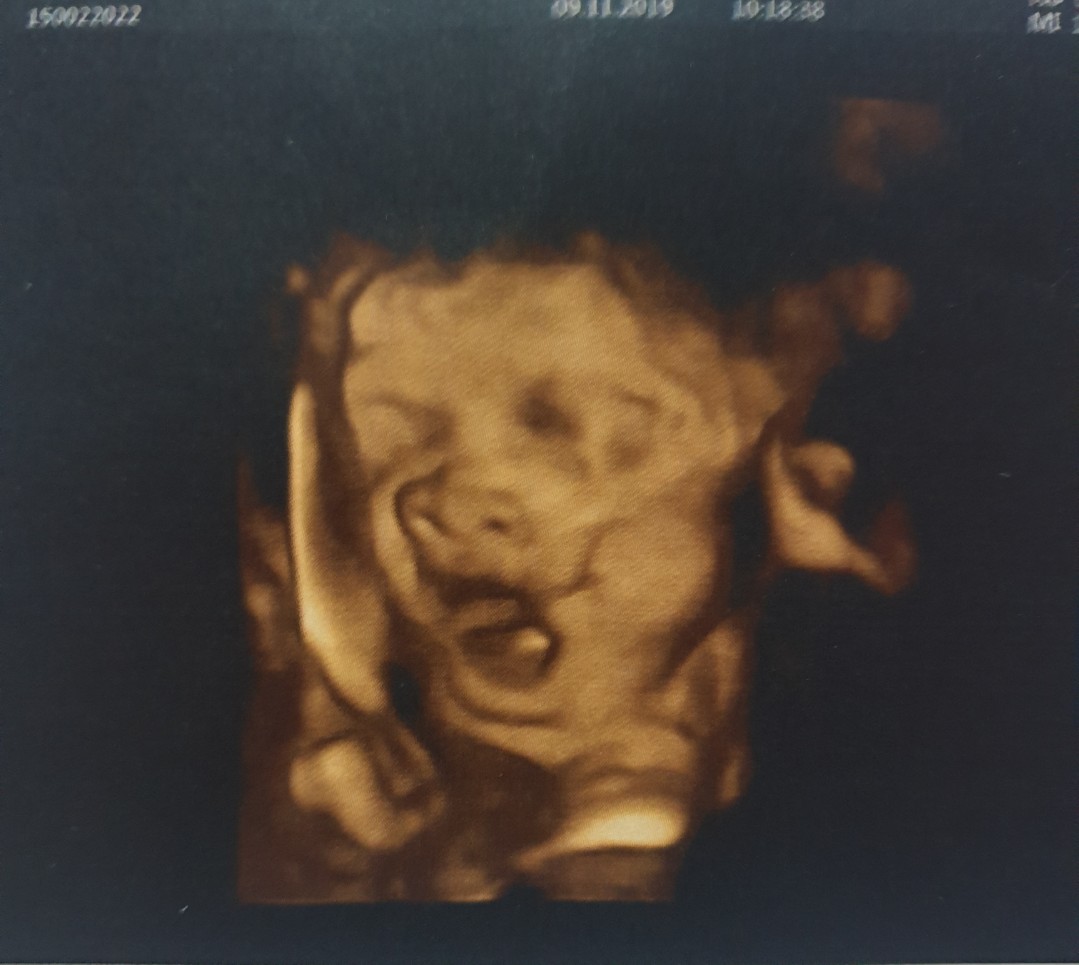

นางหาววววว..ใส่ แม่กับหมอ .. แม่ขอดูหน้าชัดๆก็ไม่ได้😭😭